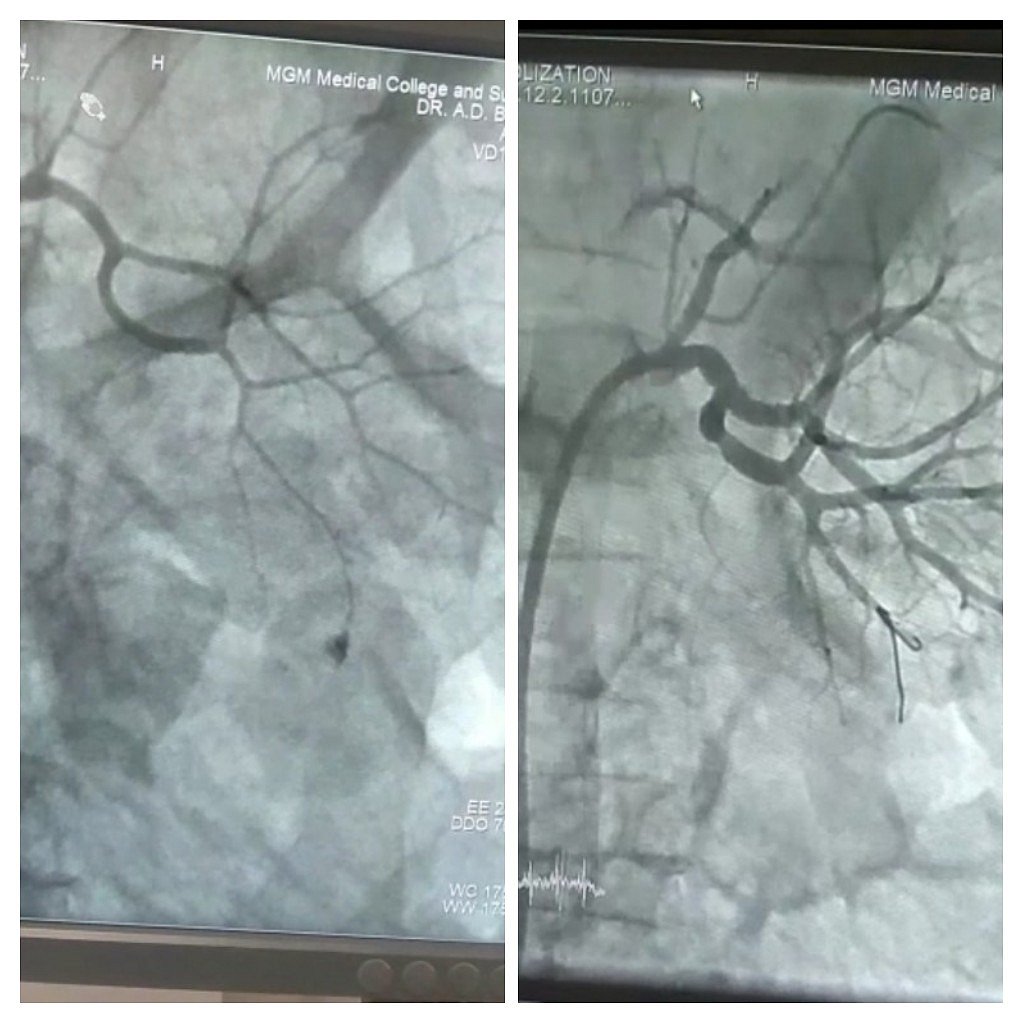

Pre coil angiography (Left) and Post coil angiography (Right) |

After evaluation, evacuation of bladder was done by urologists Dr Vishal Kirti Jain and Dr Manas Sharma immediately after which coil embolization was planned and was done by cardiologists Dr AD Bhatnagar and Dr Lokendra Rekwal in the Cath Lab at 2 am.